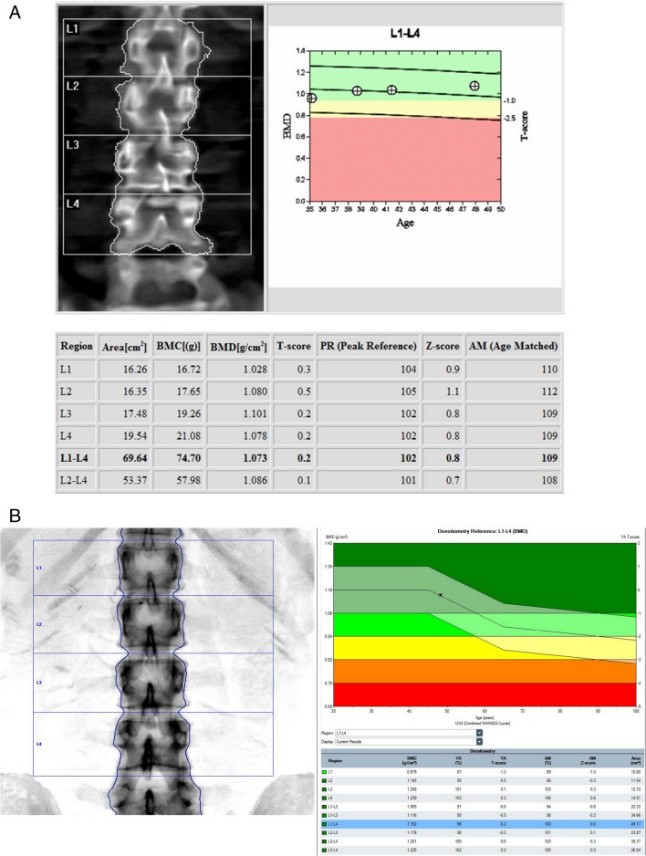

Densitometry allows you to determine the mineral density of bone tissue using x -ray radiation and predict the risk of developing fractures. The X -ray tube of the device generates a bunch of two -energy radiation. Its “soft” and “tough” components are differently absorbed by the tissues of the body and enter the detector.

In terms of size, thickness and density of the bones, the coefficients of T-criteria are calculated (comparing the patient's data with an indicator of a healthy young person of the corresponding gender) and Z-criterion (comparison with the population of the same gender, weight and age). Densitometry is a highly sensitive method that allows you to detect the minimum loss of bone matrix density (up to 2 %) with a low measurement error. Repeated densitometry is recommended using the same equipment on which the initial examination was performed, with a frequency once a year.